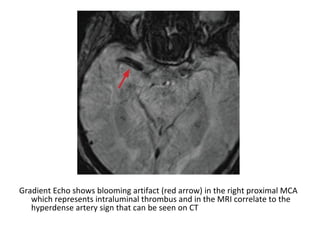

Gradient Echo shows blooming artifact (red arrow) in the right proximal MCA

which represents intraluminal thrombus and in the MRI correlate to the

hyperdense artery sign that can be seen on CT